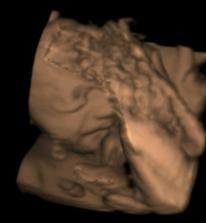

..Matulka se narodil 1.7.08 (36+4), vážil 3,18kg, měřil 50 cm, což nebylo málo 🙂 Pár hodin po porodu se ale vyskytly komplikace, pomalu se mu vstřebávala plodová voda, proto byl umístěn do inkubátoru a napojen na kyslík. Měl potíže i se zažíváním, takže mu byla podávána výživa kapačkami. PO dvou dnech mu začaly sestřičky dávat moje mlíčko stříkačkou a Matulka se začal lepšit. Nicméně zhubnul přes 40 dkg, a byl hodně vyčerpaný. V inkubátoru strávil týden. Po té ho dali do postýlky, ale pořád přespával u sestřiček na novorozenecké JIPce. CHodila jsem za ním každé tři hodky, kdo zažil, ví, kdo nezažil toho děsit nebudu, ale vzpomínky na tuto dobu nemám nejpříjemnější. Další týden jsem si ho pak mohla ´půjčovat´ - vlastní děťátko.. Bylo to nejkrutějších 14 dní v mém životě. Nicméně ted je Matulkovi skoro 8 týdnů a všechno dohnal, v lecčem je dokonce napřed. Je to velmi živé, veselé a věčně hladové miminko 🙂 uf uf .)